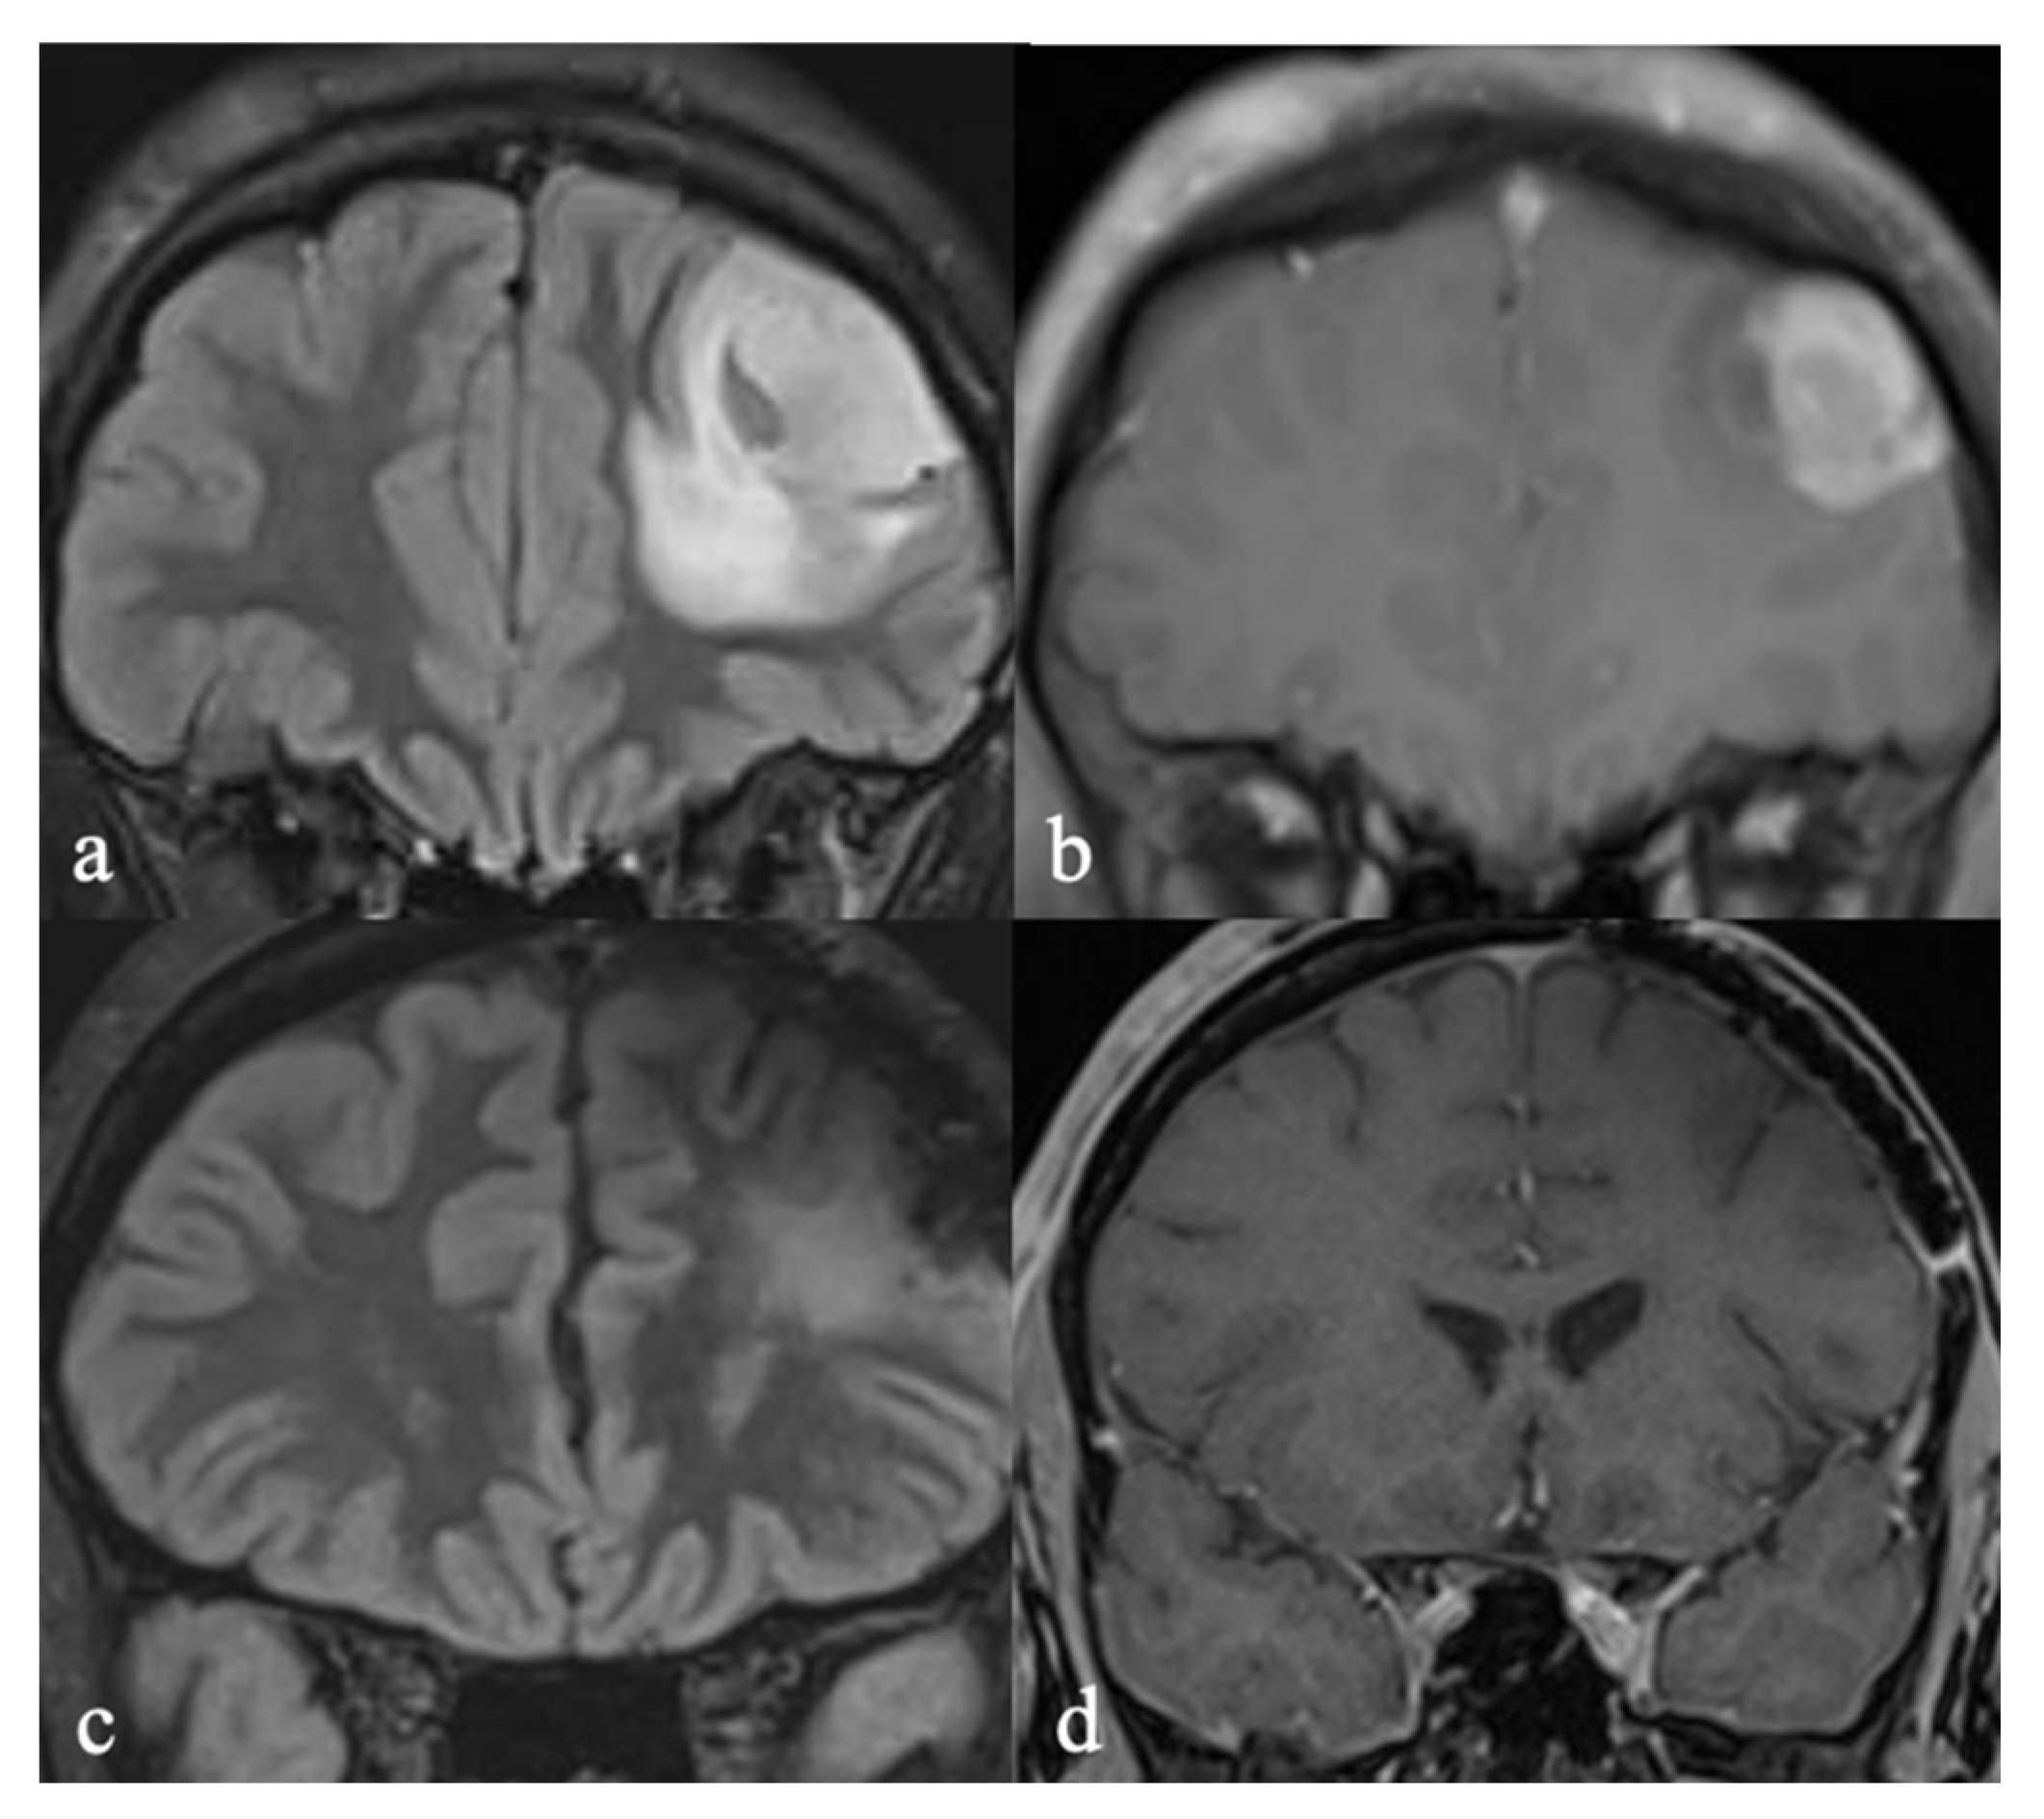

3.3. Case 3: Oligodendroglioma to Glioblastoma

3.3.1. Initial Diagnosis

3.3.2. Molecular Profiling and Treatment Timeline

| 3 | Anaplastic oligodendroglioma → GBM with oligodendroglial component | 40/F | 4 | IDH mutant, 1p/19q codeletion, MGMT 11% methylated | >20 years (10 years therapy-free) | No deficits | EQ-VAS: 70%; Distress: 3/10; EQ-5D-5L: Pain: moderate problems | 90 |